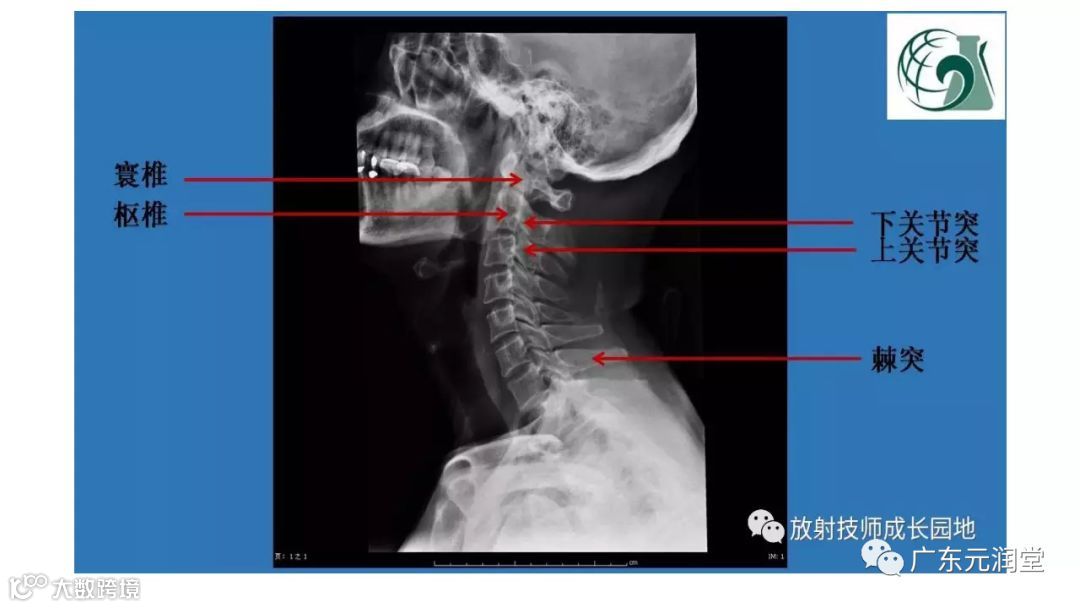

导读:X线检查操作规范之脊柱篇

X线检查操作规范之脊柱篇(值得收藏)